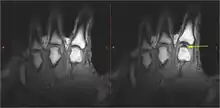

There were several hypotheses to explain the cracking of joints. Synovial fluid cavitation has some evidence to support it.[10] When a spinal manipulation is performed, the applied force separates the articular surfaces of a fully encapsulated synovial joint, which in turn creates a reduction in pressure within the joint cavity. In this low-pressure environment, some of the gases that are dissolved in the synovial fluid (which are naturally found in all bodily fluids) leave the solution, making a bubble, or cavity (tribonucleation), which rapidly collapses upon itself, resulting in a "clicking" sound.[11] The contents of the resultant gas bubble are thought to be mainly carbon dioxide, oxygen and nitrogen.[12] The effects of this process will remain for a period of time known as the "refractory period", during which the joint cannot be "re-cracked", which lasts about 20 minutes, while the gases are slowly reabsorbed into the synovial fluid. There is some evidence that ligament laxity may be associated with an increased tendency to cavitate.[13]

In 2015, research showed that bubbles remained in the fluid after cracking, suggesting that the cracking sound was produced when the bubble within the joint was formed, not when it collapsed.[9] In 2018, a team in France created a mathematical simulation of what happens in a joint just before it cracks. The team concluded that the sound is caused by bubbles' collapse, and bubbles observed in the fluid are the result of a partial collapse. Due to the theoretical basis and lack of physical experimentation, the scientific community is still not fully convinced of this conclusion.[3][14][15]